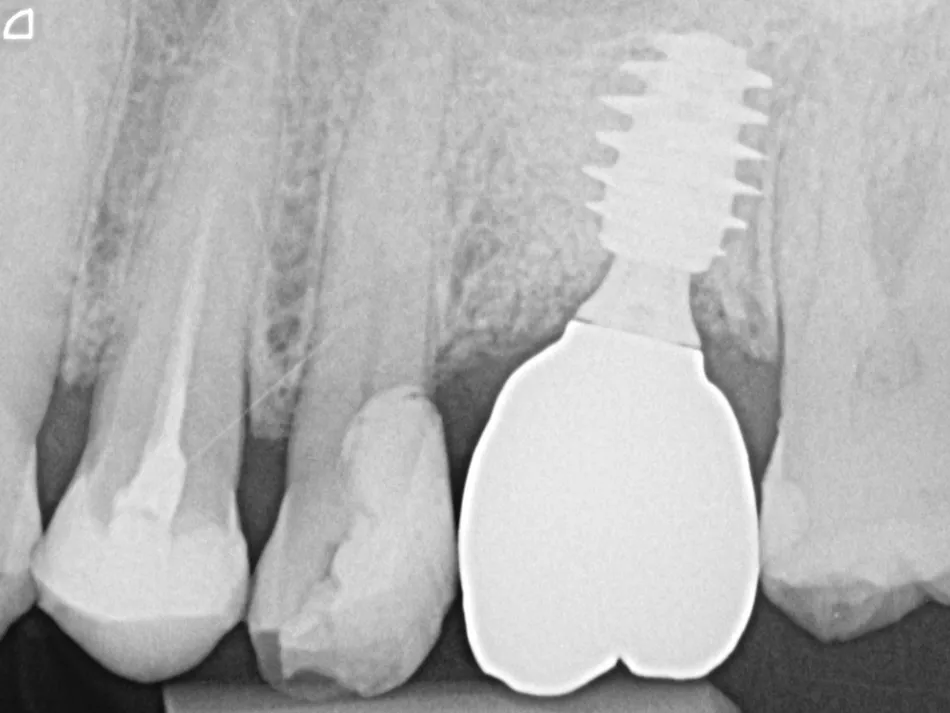

11a. 11b. Radiographs of the SSA in place and scan body for digital impressions.

11a

11b